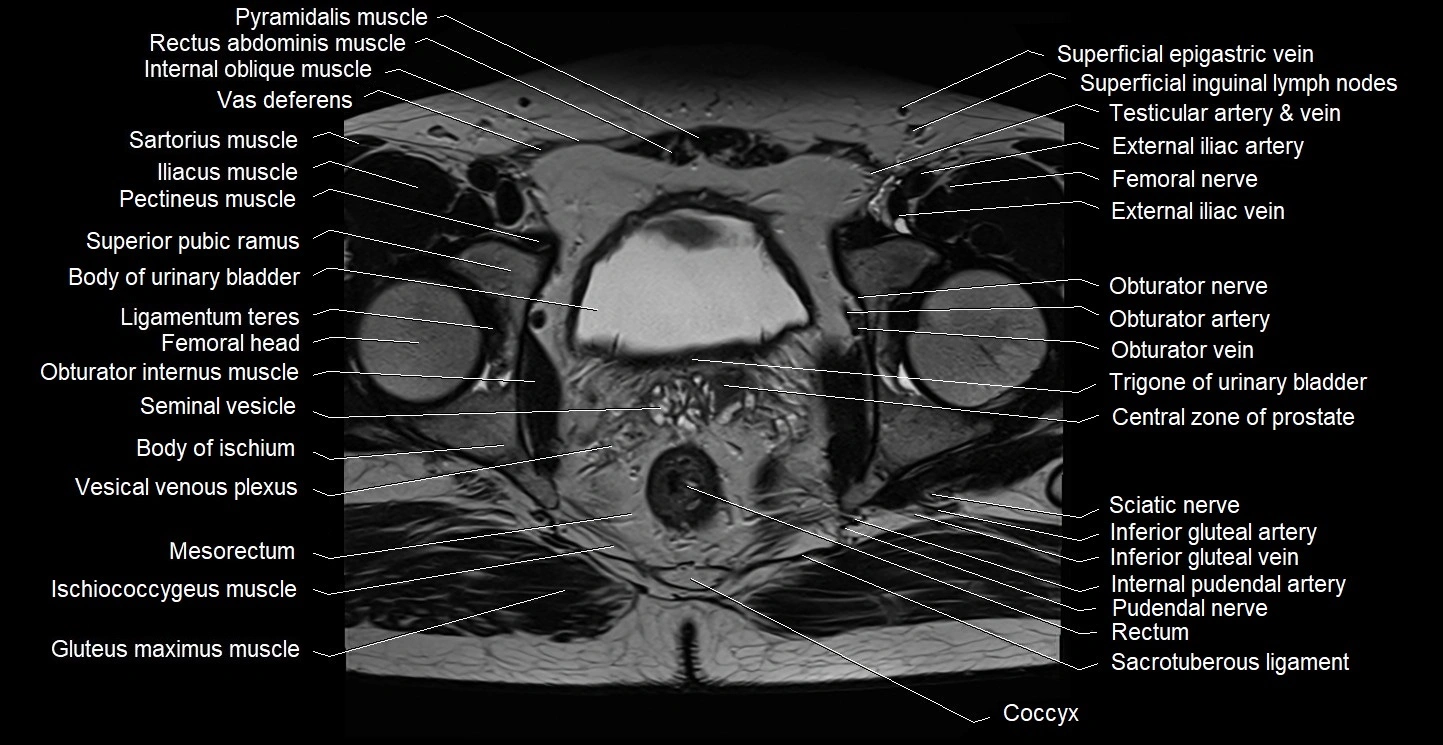

- Body of ischium

- Body of urinary bladder

- Central zone of prostate

- Coccyx

- Gluteus maximus muscle

- Gracilis muscle

- Iliococcygeus muscle

- Ischiococcygeus muscle

- Mesorectum

- Obturator internus muscle

- Obturator nerve

- Pectineus muscle

- Pubic symphysis

- Pudendal nerve

- Rectum

- Sacrotuberous ligament

- Sciatic nerve

- Seminal vesicle

- Superior pubic ramus

- Trigone of urinary bladder

- Vesical venous plexus